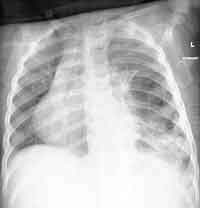

Two days later, she was afebrile, and off supplemental oxygen. The pleural

fluid culture was positive for non-typable H influenza and it was sensitive

to ceftazidime, cefuroxime, and septra. Clindamycin was discontinued

and the chest tube was removed on the 6th day. Now, after 2 weeks of

intravenous antibiotics, she was looking well and dramatically improved

clinically. Her WBC was normal and she was discharged home off antibiotics.

BELOW IS HER CHEST RADIOGRAPH ON DISCHARGE.

ENLARGE the chest X-ray

WHAT IS YOUR INTERPRETATION?